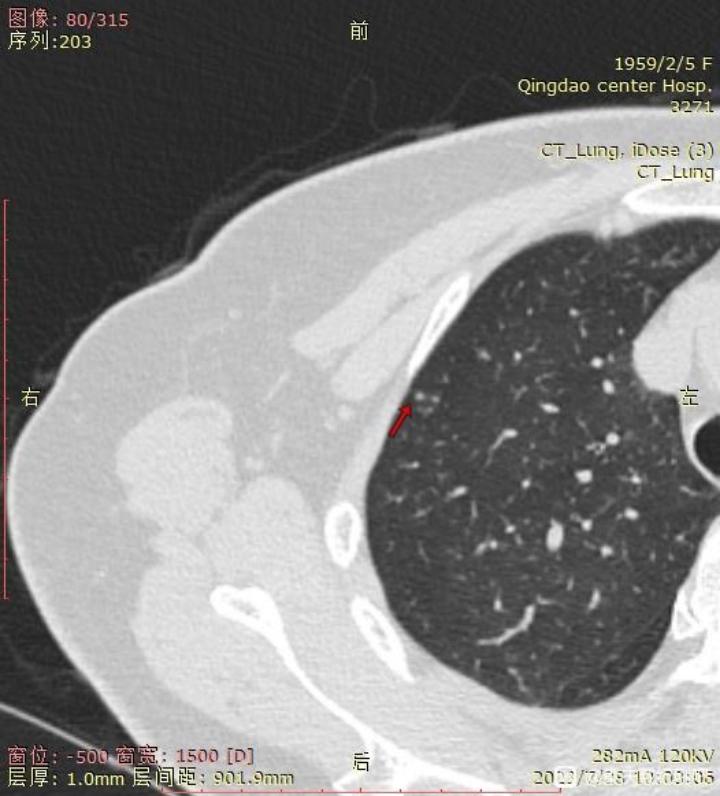

右肺未切除结节截图:

1. 右肺上的小结节是哪一种类型,如果真不好的话,消融可以吗?毕竟刚手术完,无法近期再手术。

右肺结节没啥事。左肺结节根治率85-90%.不需要后续治疗